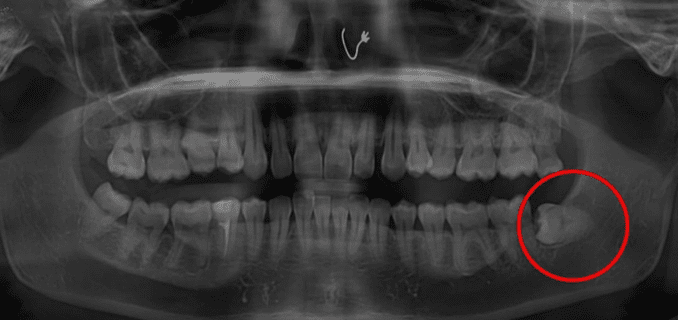

Wisdom Tooth Removal-2

Wisdom Tooth Removal-1

Examination & X-ray

Dentist evaluates position of tooth and surrounding structures.